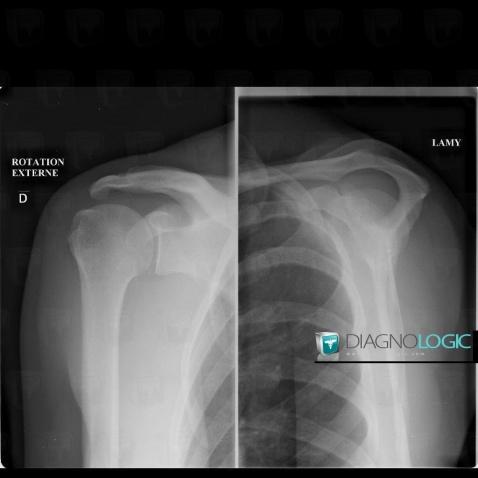

Tendinopathy / Shoulder, Sub scapularis tendon, X rays

Here is the specific information in the key image above:

- Diagnosis Rotator cuff tendinopathy / Shoulder, Location(s) Sub scapularis tendon, with gamuts